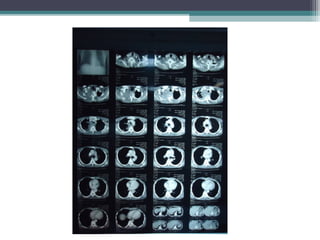

• TC de tórax

• TC de Tórax (03/07/12)

EXAMES COMPLEMENTARES • TCde Tórax (03/07/12)  Massa heterogênea com áreas de necrose em permeio medindo cerca de 9,0x 12 cm, localizada em ápice de pulmão direito, sem planos de clivagem com estruturas mediastinais adjacentes  Notam-se lesões osteolíticas em corpos vertebrais dorsais superiores e costelas adjacentes, além de invasão da parede torácica deste lado  Linfonodos aumentados predominantemente em espaço pré- traqueal  Achados descritos sugestivos de processo blastomatoso primário de pulmão